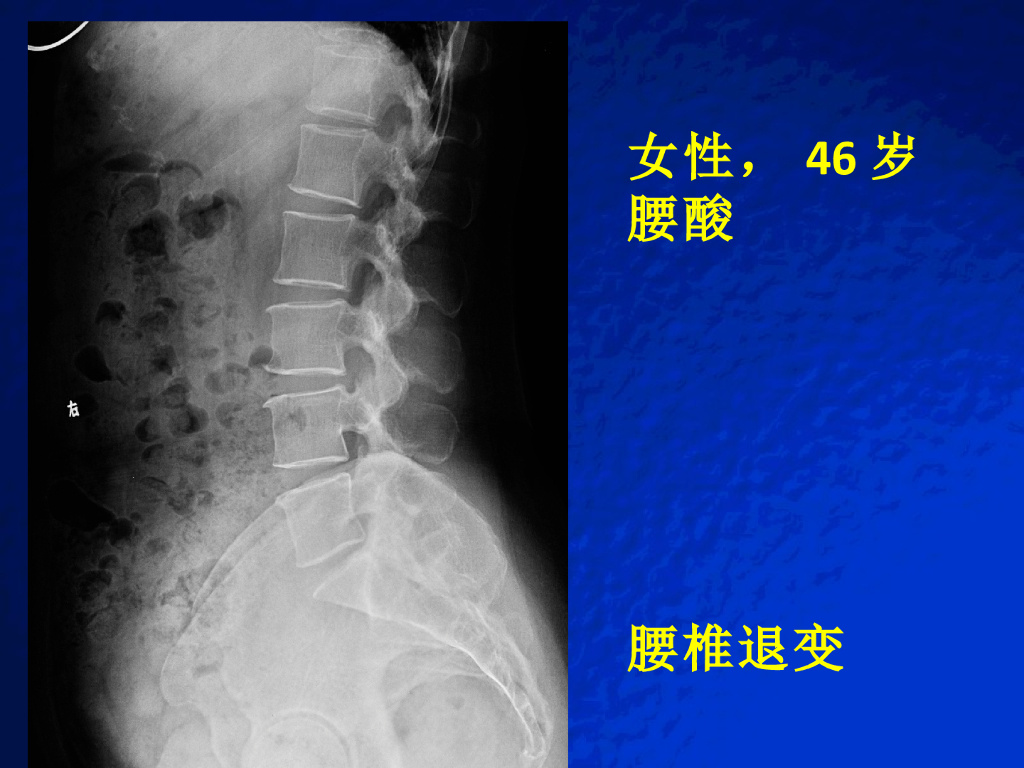

《放射诊断学》演示文稿-脊柱与软组织病变实习课.pdf